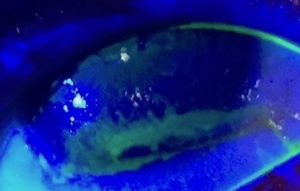

- Slit lamp examination with and without fluorescein dye staining (Rose Bengal and Lissamine green may also be used). Prior to staining assess for external signs as outlined below. Early EK is characterized by corneal desiccation and upon administration of fluorescein dye superficial punctate epithelial staining, most commonly localized to the inferior one third of the cornea becomes apparent (Figure 6).[7] These microepithelial defects may coalesce into an abrasion or progress to form an ulcer or infiltrate.[7] Assess for external signs as outlined below.

Complications include corneal abrasion, ulceration, microbial keratitis, perforation and corneal scar leading to vision loss (Figure 8).[32] Additionally, band keratopathy may present as a complication of chronic EK.[33]